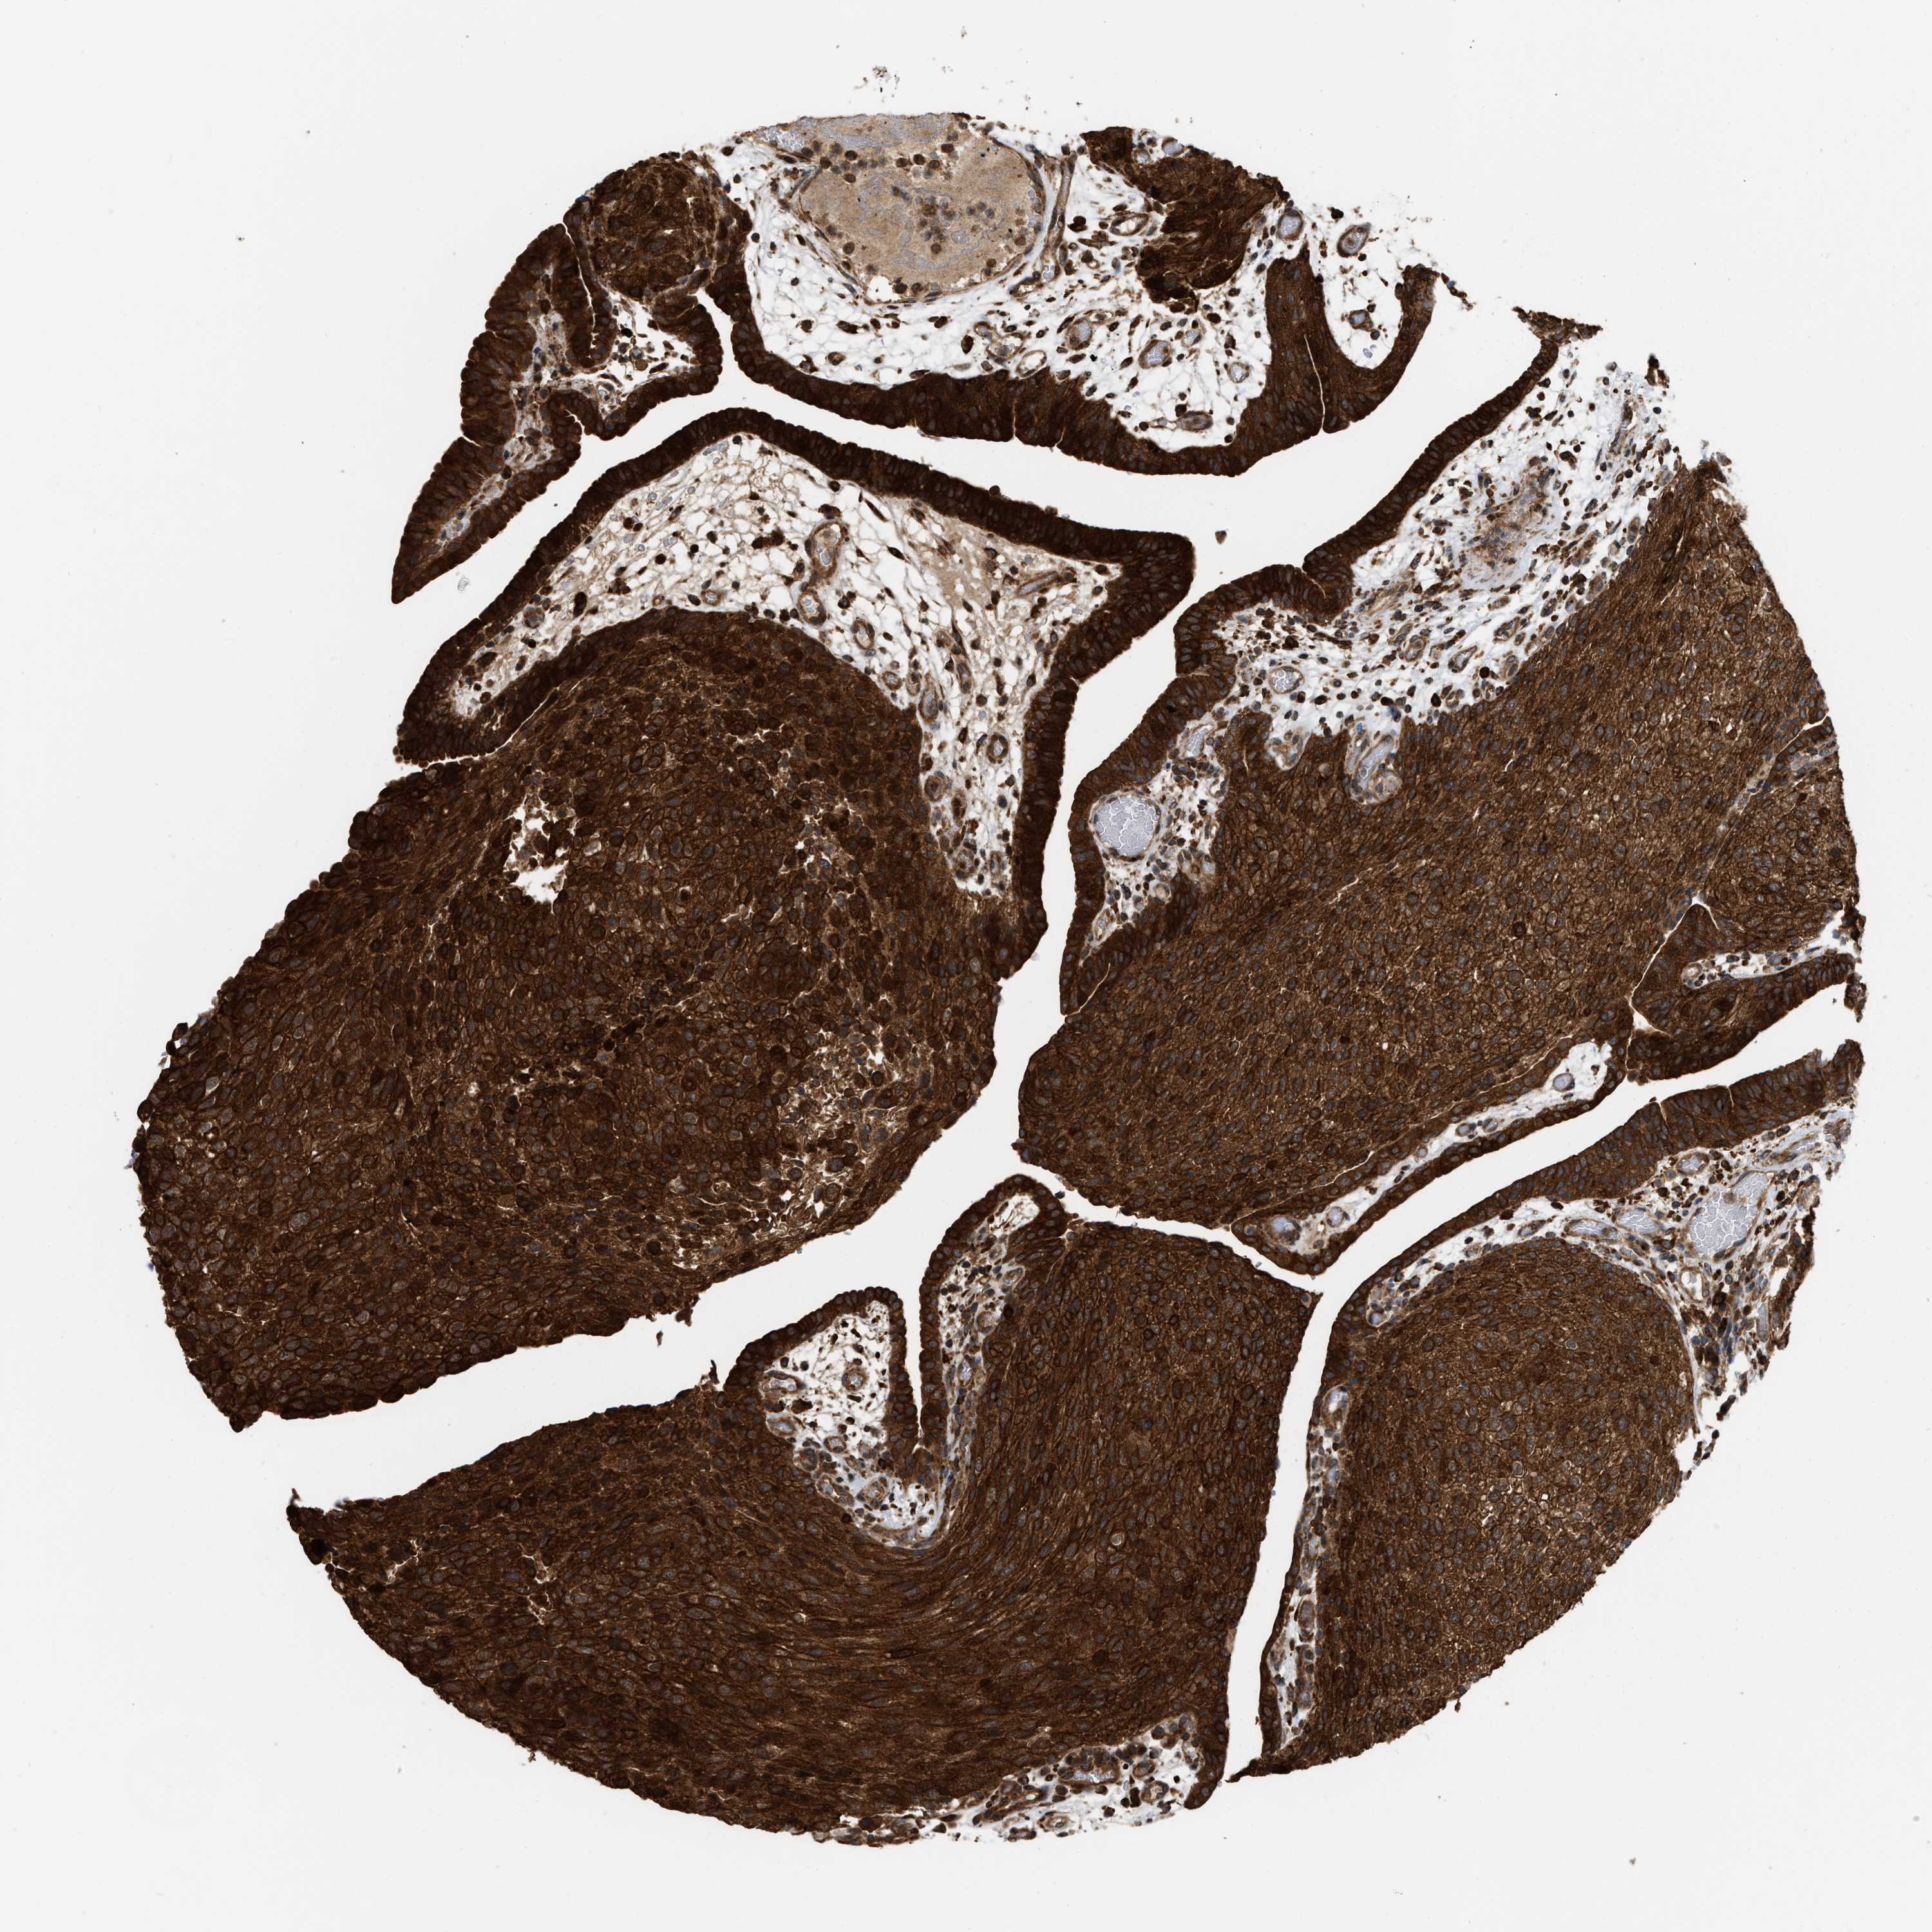

UROTHELIAL CANCER - Protein expressioni

A mouse-over function shows sample information and annotation data. Click on an image to view it in a full screen mode. Samples can be filtered based on level of antibody staining by selecting one or several of the following categories: high, medium, low and not detected. The assay and annotation is described here.

Note that samples used for immunohistochemistry by the Human Protein Atlas do not correspond to samples in the TCGA dataset.

Antibody stainingi

Antibody staining in the annotated cell types in the current human tissue is reported as not detected, low, medium, or high, based on conventional immunohistochemistry profiling in selected tissues. This score is based on the combination of the staining intensity and fraction of stained cells.

Each image is clickable and will lead to virtual microscopy that enables deeper exploration of all samples and also displays staining intensity scores, fraction scores and subcellular localization as well as patient and tissue information for each sample.

Antibody HPA019515

Staining

High

Medium

Low

Not detected

Intensity

Strong

Moderate

Weak

Negative

Quantity

>75%

75%-25%

<25%

None

Location

Urothelial carcinoma, Low grade

Urothelial carcinoma, High grade